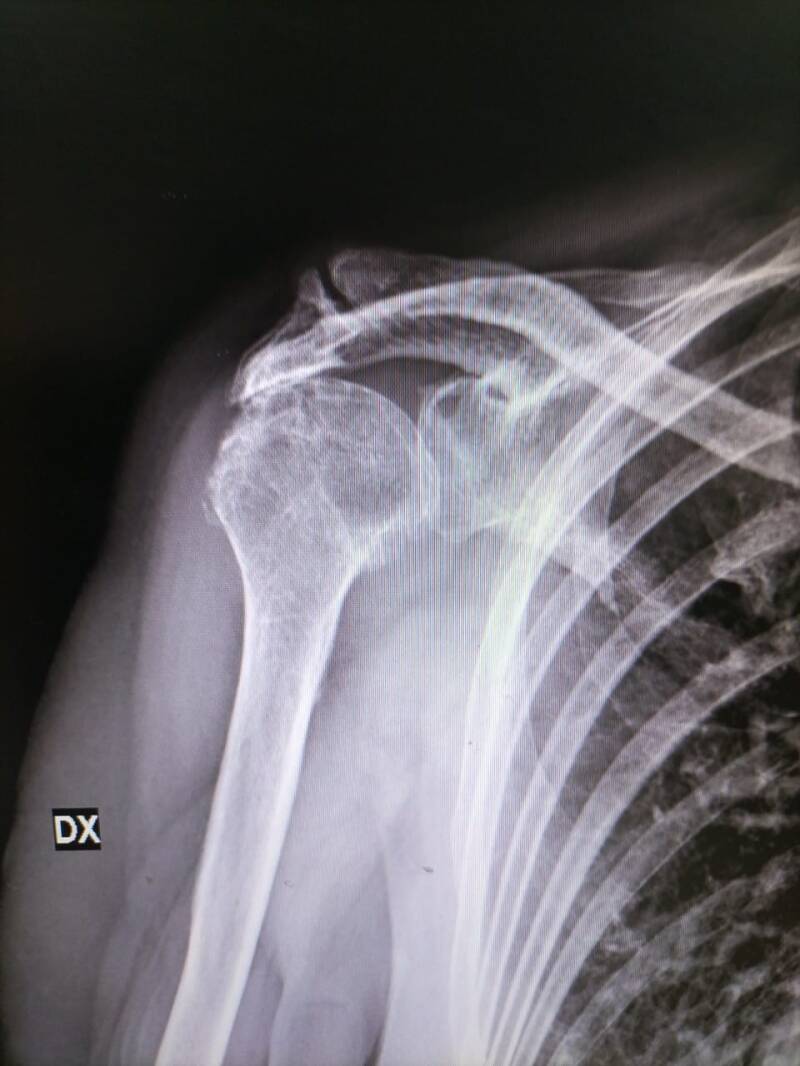

L’artropatia della cuffia dei rotatori è una malattia con una evoluzione lenta ma continua.

Il processo degenerativo prevede:

- il consumo della cartilagine della spalla;

- lo sfregamento delle ossa dell’articolazione scapolo omerale.

Questo tipo di problematica si sviluppa a seguito di patologie come l’artrite reumatoide ma può svilupparsi anche in seguito a frattura della spalla e/o lesioni da trauma alla spalla a seguito della non idonea consolidazione di una frattura alla spalla o di un ispessimento dei tendini della cuffia.

In pratica in un’articolazione sana le superfici articolari della testa omerale e della glena sono protette e rivestite di cartilagine, ciò permette ai capi articolari di muoversi senza generare attrito tra le ossa.

L’artropatia della cuffia dei rotatori si presenta in soggetti predisposti oppure oltre i 65 anni e può prevedere come causa non solo dolore e rigidità articolare ma anche lesioni tendinee; nei casi più gravi l’intervento chirurgico di protesi inversa di spalla è una delle soluzioni più indicate per la ripresa delle attività quotidiane.

I sintomi di un’artropatia della spalla sono:

- dolore;

- impossibilità di muovere il braccio e/o la spalla;

- degenerazione progressiva del tessuto tendineo;

- degenerazione progressiva del tessuto cartilagineo;

- cedimenti della cuffia con perdita di funzionalità della spalla e/o del braccio.